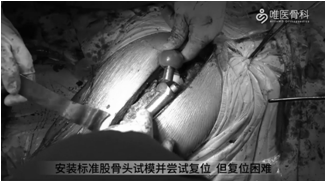

②根据臼杯前倾,调整股骨前倾,使联合前倾角在安全范围内。安装标准股骨头试模,并尝试复位,但是复位困难。遂给予依次组装不同尺寸的假体试模并进行复位,以确定合适的下肢长度、稳定性和偏距。